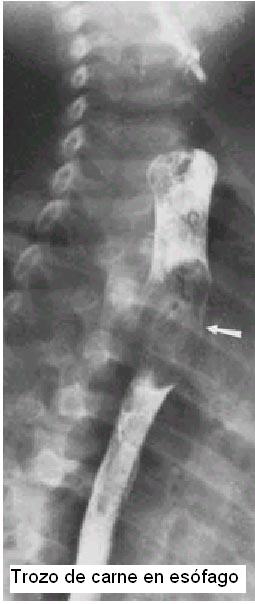

2) En adultos lo mas frecuente es huesos de pollo, espinas de pescado, carne en trozos mal masticados por mala dentición(en adultos mayores).

Rx simples de perfil de cuello con técnica para partes blandas en hiperextensión son de utilidad para objetos radio opacos.

Con un trago de bario si la rx simple sugiere un c/ extraño radio lúcido.

Manejo de cuerpos extraños de esófago:

1) Diagnóstico clínico-rx

2) Extracción por esofagoscopía rígida.